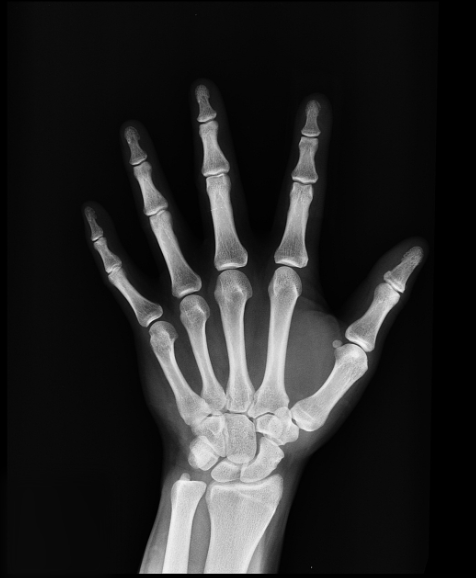

- 영상 검사: X선, CT 스캔, MRI 등을 통해 뼈의 상태를 평가하고 감염의 범위를 확인합니다.